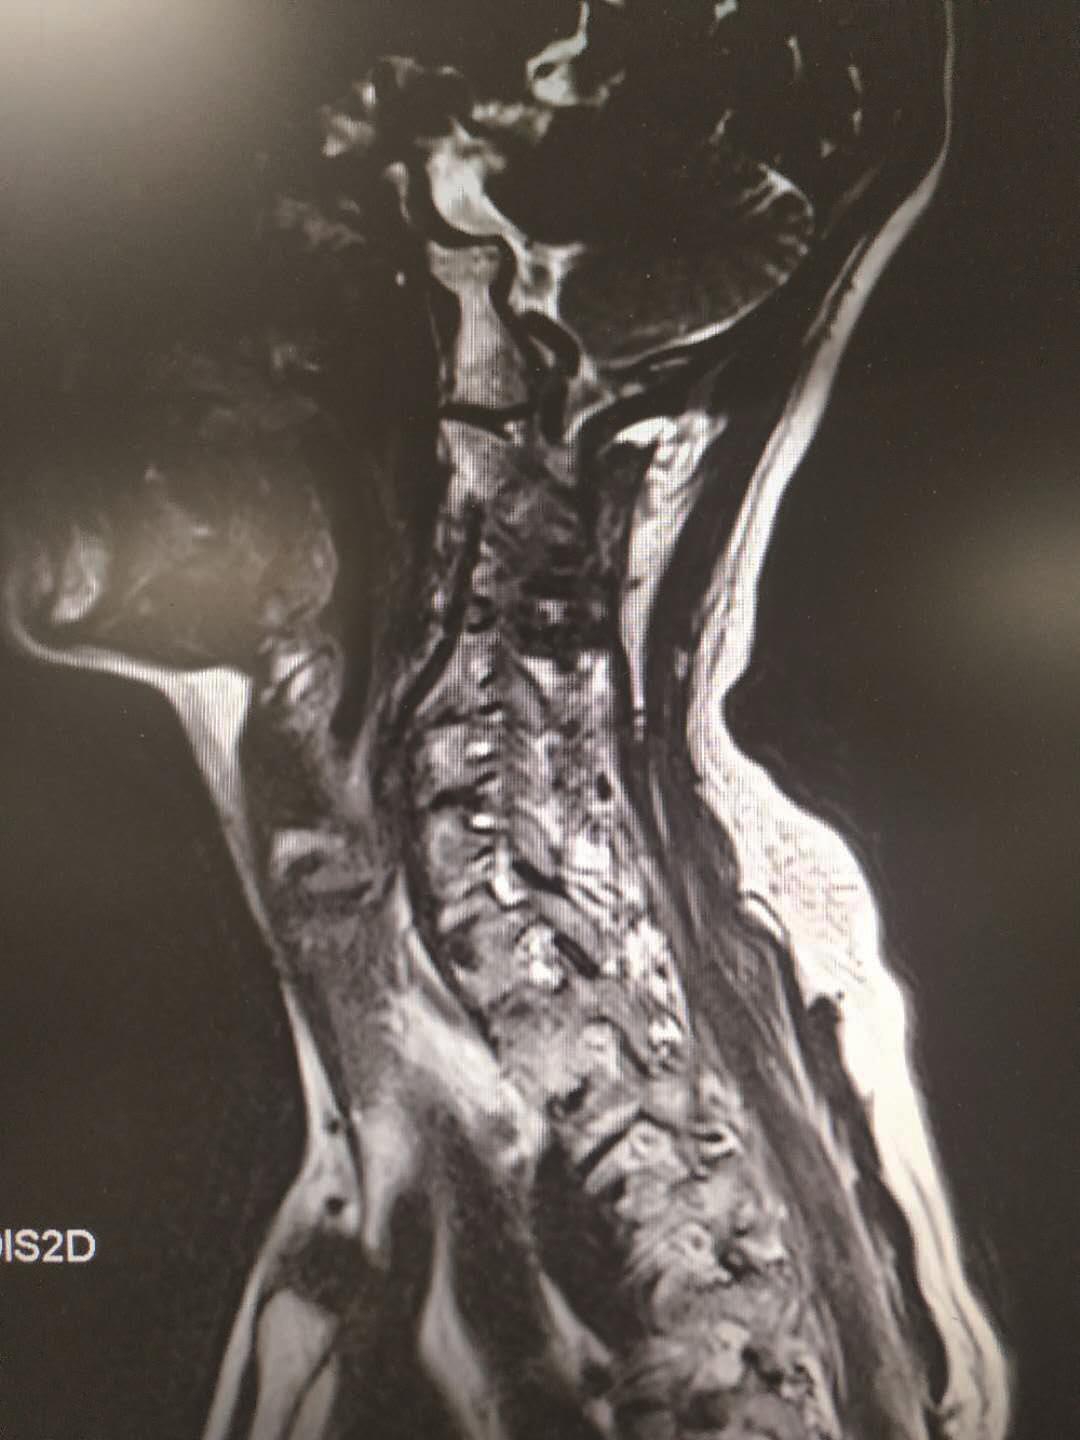

颈椎磁共振扫描可显示颈椎骨质和软组织的病理变化。